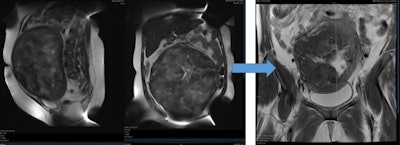

الأورام الليفية الرحمية عبارة عن أورام حميدة في الرحم يمكن لها أن تتسبب في إطالة فترة وغزارة نزف الدورة الشهرية والذي قد يكون شديداً في بعض الحالات لدرجة أنه يسبب فقر دم ويتطلب نقل دم للمريضة و اعطاء حقن الحديد.

كما قد يعاني مرضى الأورام الليفية الرحمية من ألم في الحوض يمكن أن يعيقهم عن ممارسة حياتهم اليومية، إحساس بالضغط في الحوض، تكرار التبول، ألم أثناء الجماع، إجهاضات، تأثير على الإنجاب، كما أنه قد يسبب ضخامة كبيرة في الرحم تشبه الحمل.

لوحظ أن خطورة الأورام الليفية الرحمية على الحمل ونوع الاختلاطات الناجمة له علاقة بحجمها، عددها، ومكانها. بالتأكيد فإن العقم يحدث عندما تكبر الألياف لدرجة تتسبب فيها بإغلاق أحد أنبوني فالوب أو كلاهما او عندما يملء الرورم جوف الرحم.